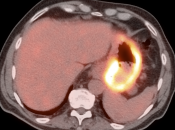

The difficulty with PET/CT imaging and gastric cancer is that it is both easy to overlook and easy to over-call.

Normal FDG uptake involving the stomach can be extremely variable. It is not uncommon to see diffuse intense uptake throughout the entire stomach or intense uptake limited to only a segment of the stomach (fundus, body or antrum).

In general, we raise a suspicion of gastric malignancy if:

• Focal or regional hypermetabolic activity is accompanied by at least the suggestion of associated wall thickening (often difficult to assess if the patient’s stomach is suboptimally distended with water or oral contrast);

• Uptake is extremely focal (more likely to represent malignancy or ulcer);

• Focal/segmental uptake is extremely intense.

• Obviously, signs of associated metastatic disease on the scan give the radiologist much greater confidence in reporting a suspected primary gastric lesion.